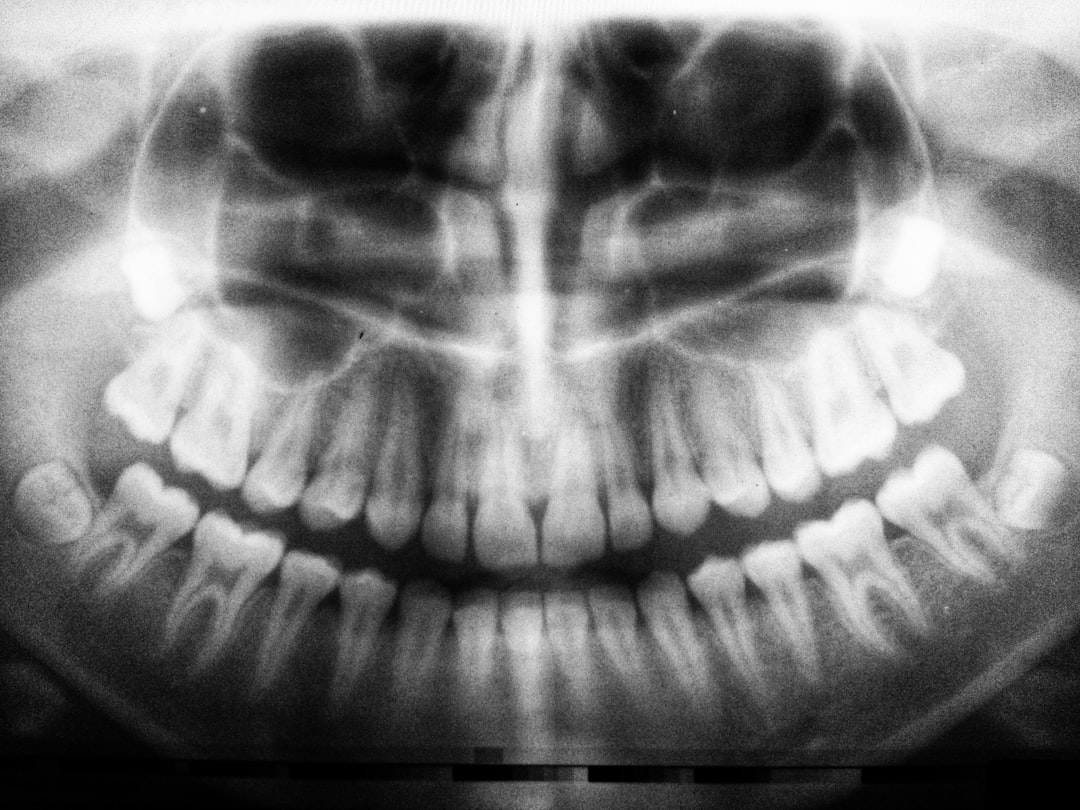

성인이 되면 성인 치아 개수는 평균 32개로 나타납니다. 상악과 하악 각각 16개가 나누어진 형태이며, 대개 4개의 사랑니가 포함됩니다. 하지만 모든 성인이 그렇듯, 어떤 사람들은 사랑니의 발달로 인해 다소 차이가 발생할 수 있습니다. 더군다나, 성년기에 접어든 시점에서 잃어버린 치아가 있다면, 남아있는 개수가 줄어드는 것이 자연스러운 현상입니다. 하지만 이는 피할 수 있는 문제이므로, 치아 개수 관리는 필요합니다.

사람의 치아 개수는 단순한 숫자로 보일 수 있지만, 그 뒤에는 구강 건강을 위해 지켜야 할 많은 비결이 숨어 있습니다. 기본적으로 사람 치아 개수는 나이와 함께 변하는 경향이 있습니다. 어린 시절에는 유치가 자리를 차지하다가 성장과 함께 영구치로 대체되면서 성인의 치아 개수가 형성됩니다. 어른이 된 후에는 구강 건강 관리에 더욱 신경 써야 하는 이유입니다. 이를 잘 지키지 않으면 나중에 불필요한 시술과 비용이 발생할 수 있습니다.

범위가 넓지만, 어린이 치아 개수는 일반적으로 20개입니다. 이 유치는 보통 6세에서 12세까지 자리를 차지하며, 이후 영구치로 대체됩니다. 어린이의 경우, 어린이 치아 개수는 구강 건강의 시작점이므로 소중하게 관리해야 합니다. 어릴 때부터 올바른 양치 습관을 들여주면 성인이 되었을 때 건강한 치아를 가질 가능성이 높습니다. 이런 초기 관리가 치아 개수를 늘리는 밑바탕이 자리를 잡을 수 있습니다.

반면, 유아 치아 개수는 더 적은 수치로, 일반적으로 10-12개입니다. 또한, 이들은 예민한 시기로, 음식이나 환경에 따라 영향을 받을 수 있습니다. 각종 음식이나 음료에 포함된 설탕이 너무 많이 섭취되면 유치가 쉽게 썩을 수 있습니다. 따라서 부모는 항상 자녀의 구강 건강에 신경을 써야 합니다. 주기적인 치과 방문과 함께 홈 케어 교육이 필수적입니다.